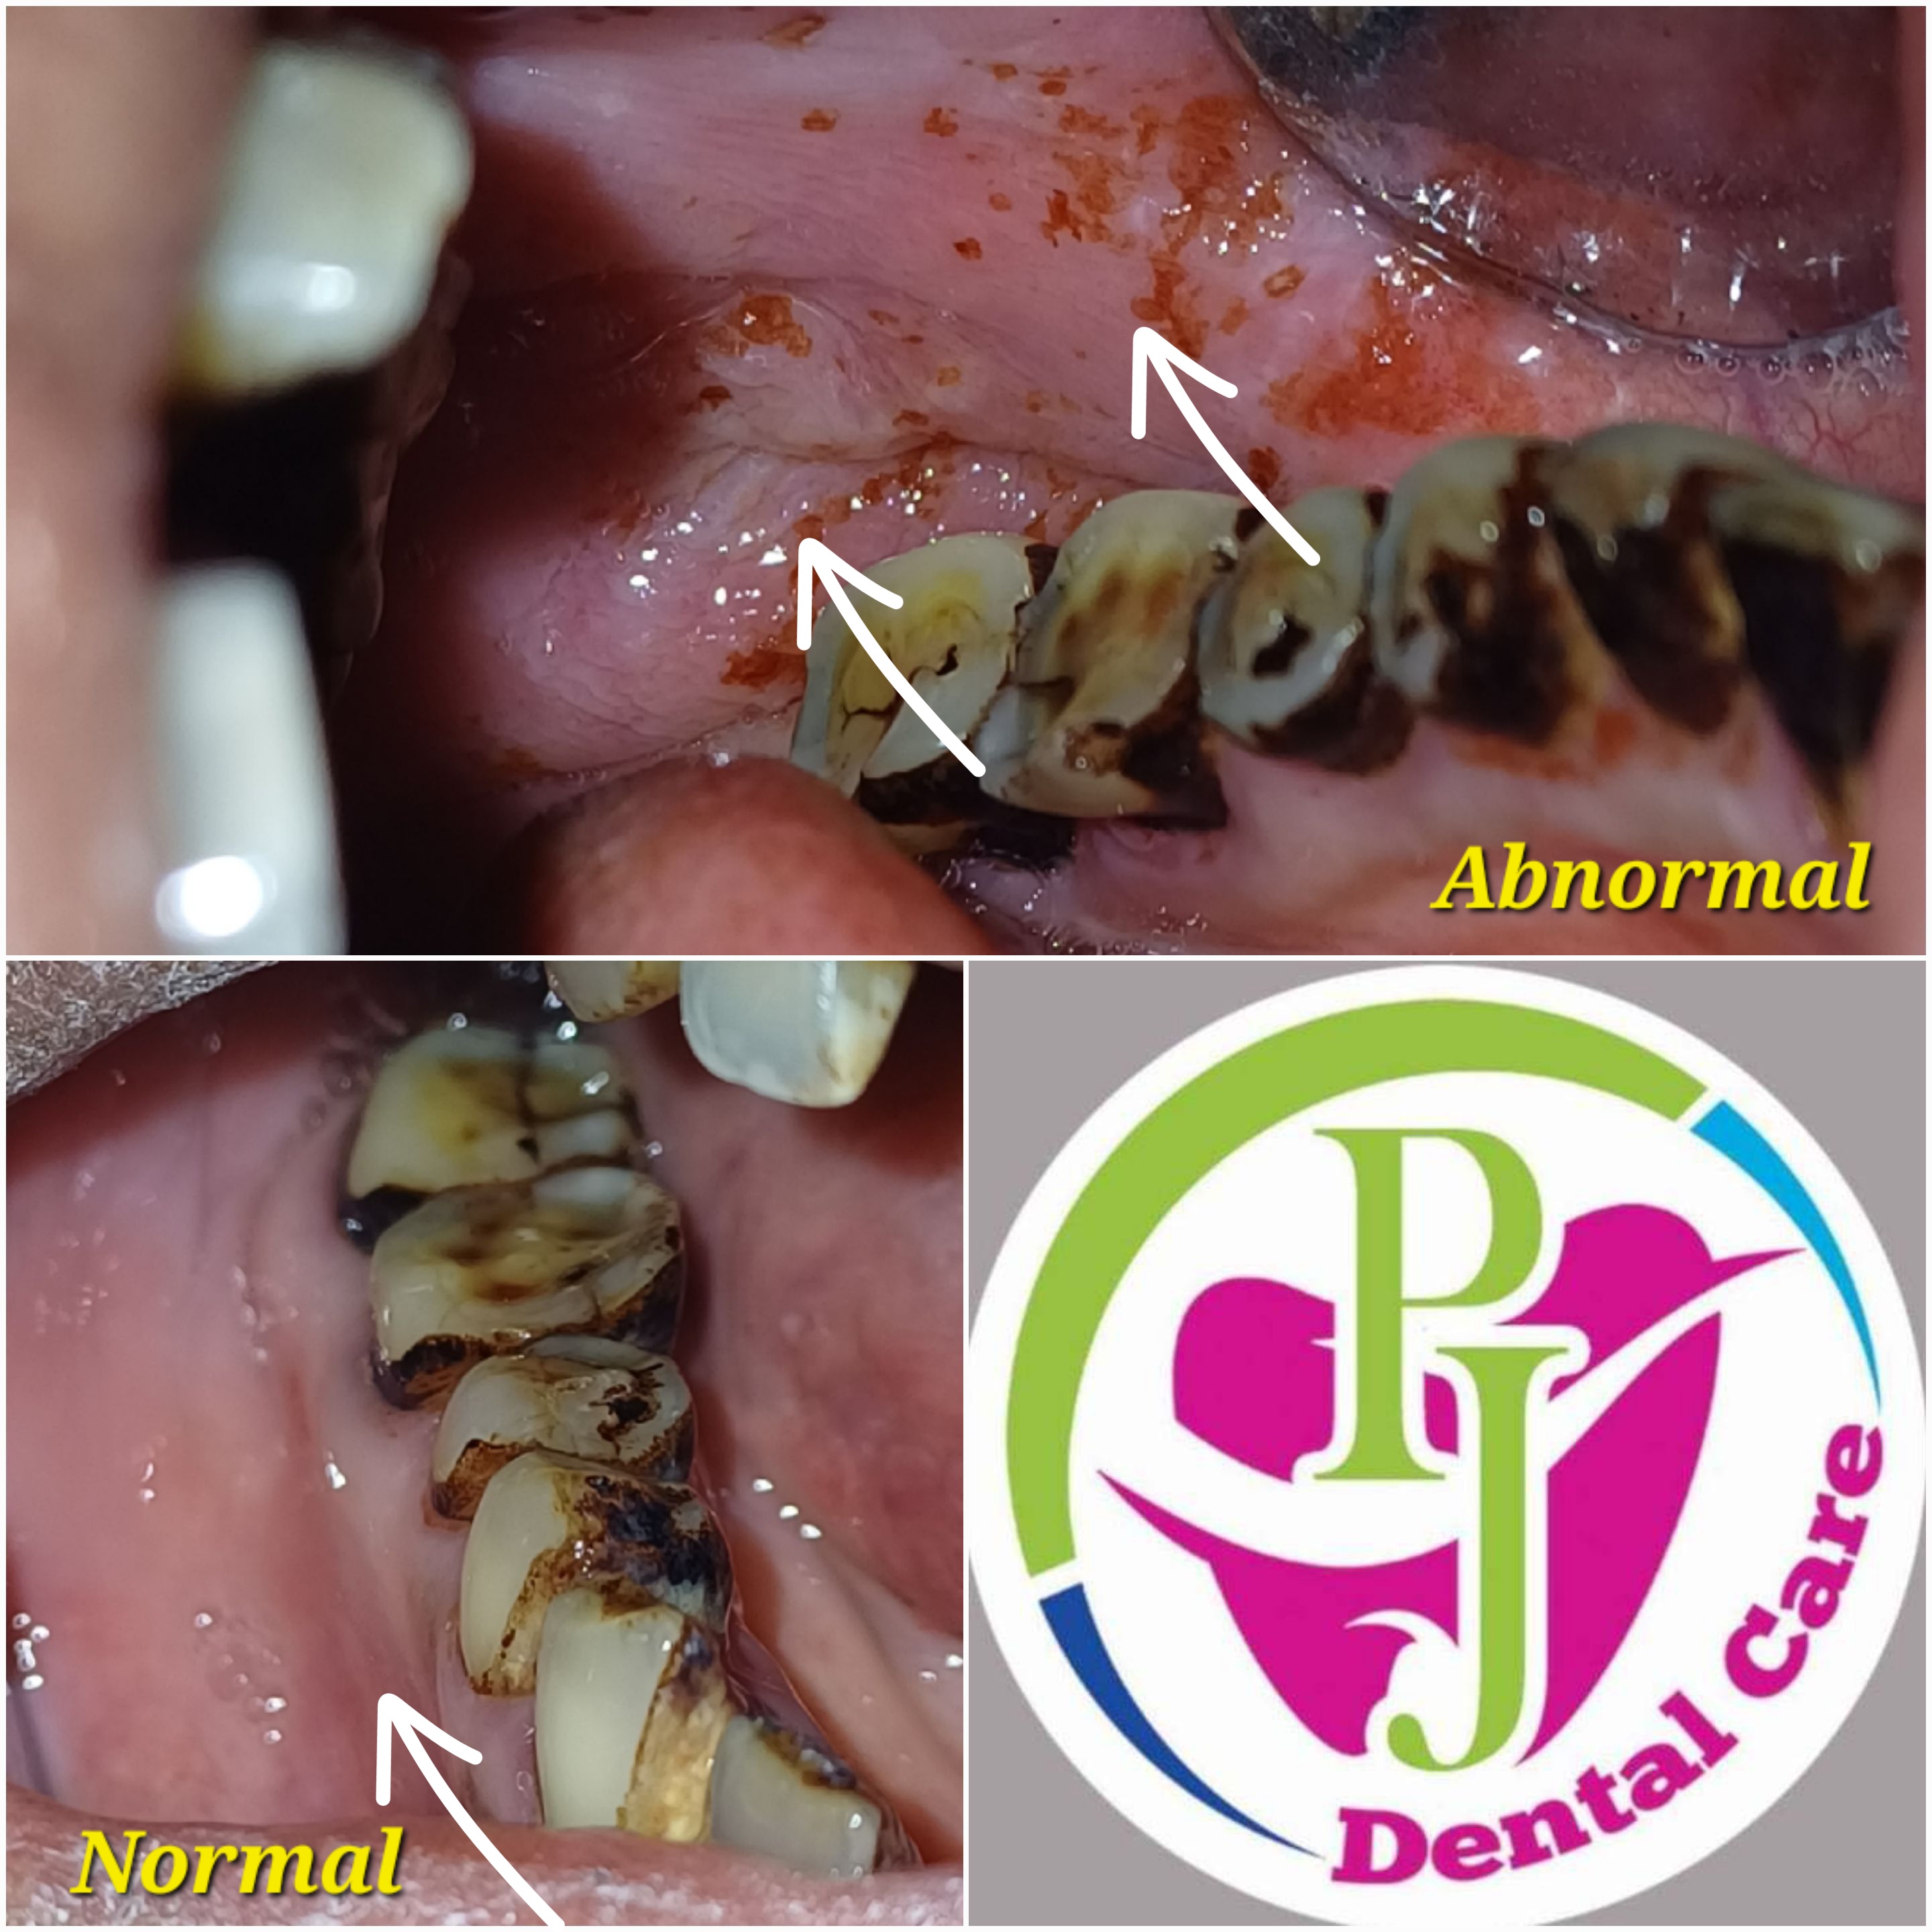

Your leading choice for dental, laser, and permanent makeup services in Tirupati. PJ Dental and Aest... hetics (Ph: 9148118616) offers affordable implants, root canals, laser hair reduction, lip blush, and more since 2012. We ensure the best treatment outcomes at reasonable prices. Read more